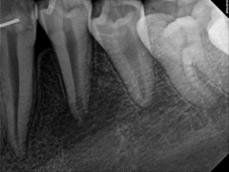

Every tooth has different numbers of roots and canal systems. With the help of magnification and high tech equipment, Dr. Jung can locate and treat the canals including MB2 on upper molars and MM on lower molars.